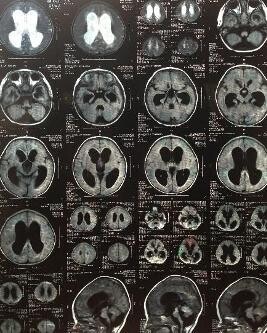

急性化膿性腦膜炎